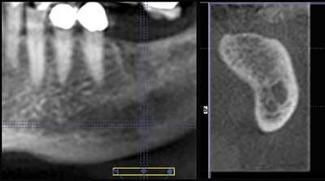

The small detail that “isn't so” can deter the successful outcome of an implant procedure. General practitioners must be armed with the most detailed information possible that can increase their comfort level in placing implants. Sometimes, a 2-D pan cannot provide insight into the 3-dimensional shape of the bone, which is imperative when placing implants. Some anomalies just can't be discerned in two dimensions, and 3-D technology adds depth to our diagnosis, planning, and success. My GXCB-500, which scans just the areas I need as a general dentist, delivers this information. A colleague and fellow “500” owner, Dr. Gary Henkel of Horsham, Pa., shared some images of a patient where 3-D saved the day.